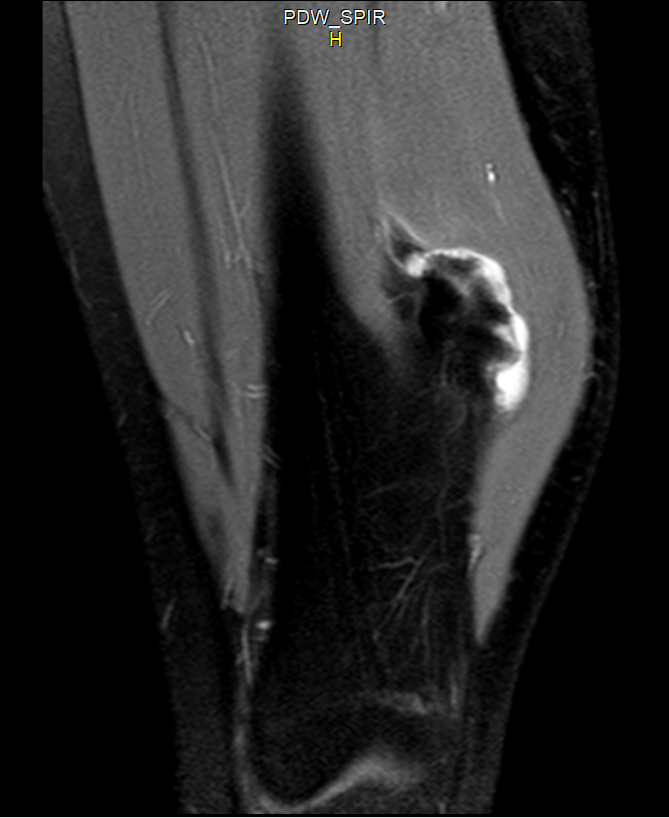

1.4.2 TC y RM

- 🩻 RM: clave para medir el capuchón cartilaginoso (hiperintenso en T2/STIR) y valorar bursitis/compresión neurovascular. Es la prueba más útil ante sospecha de transformación.

- ⚠️ Capuchón cartilaginoso engrosado en RM:

- 🔹 En adultos, un capuchón >2 cm es muy sospechoso.

- 🔹 En niños/adolescentes puede ser más grueso sin malignidad; la interpretación debe ser clínica y evolutiva.